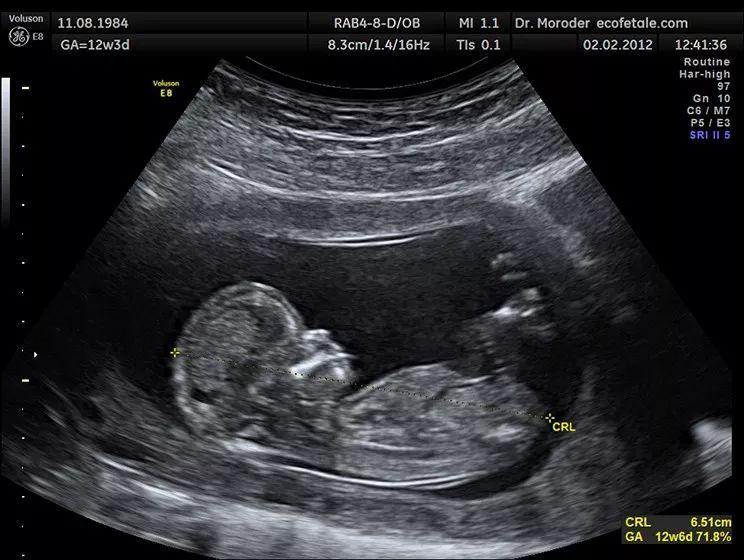

酒钢医院超声科最新引进世界先进超声设备——美国ge-volonsone10彩超

图片尺寸1125x1500